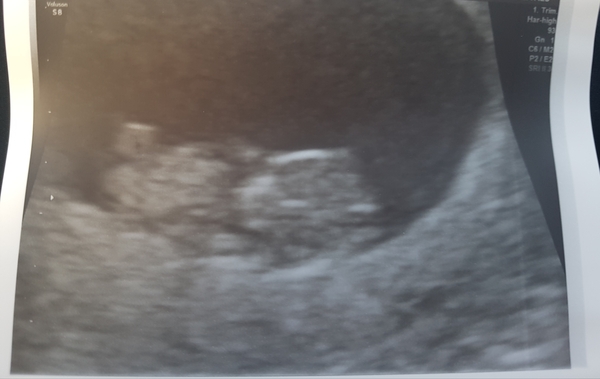

Pancakes7 · 20/10/2018 13:29

Scan went well! We heard the heartbeat. Baby was wiggling and it's little arm was up. Placenta isn't fully formed yet but its growing. Not sure which side it was as she flipped it round in the pics.

9 weeks +2 scan

Great scan pic @Pancakes7 can really see a little baby there! Hearing the heart beat must be so amazing!

@Pancakes7 congrats on your scan! Beautiful picture.